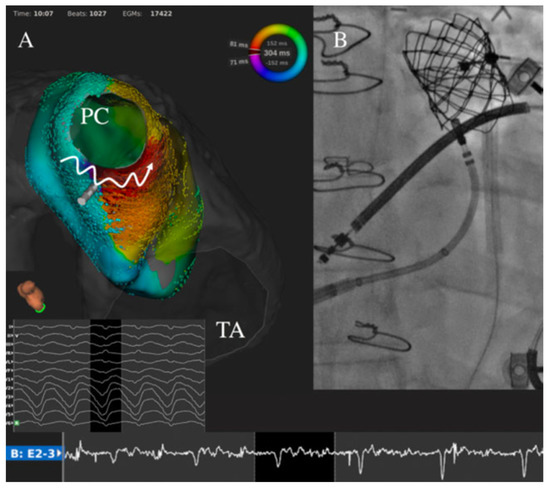

- Laredo, M.; Waldmann, V.; Soulat, G.; Amet, D.; Marijon, E.; Iserin, L.; Ladouceur, M.; Zhao, A. Transbaffle/Transconduit Puncture Using a Simple CARTO-Guided Approach without Echocardiography in Patients with Congenital Heart Disease. J. Cardiovasc. Electrophysiol. 2020, 31, 2049–2060. [Google Scholar] [CrossRef] [PubMed]